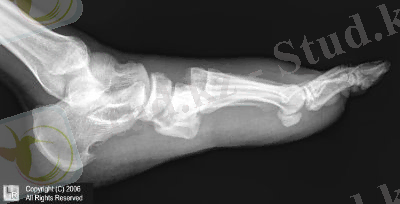

10-сурет: Лисфранк буынында сол жақтан біржақты толық шығуы

Жарақат механизмі: тура (табанның алдыңғы бөліміне соққы не құлау) Табан сүйектерінің жекеленген сынықтары үшін ығысу аса тән емес, көптеген сынықтар ығысумен жиі жүреді.

Диагностикасы: табанның сыртқы бетінде ауырсыну және ісіну. Табан сүйектеріне осьті жүктеме және жергілікті пальпация ауырсынумен жүреді. Якобсон симптомы -табан сүйегі басын басқанда сынған жерде ауырсыну.

Радиологиялық зерттеу: Екі проекцияда жүргізіледі

Емі: Табан сүйектерінің ығысусыз сынықтарында консервативті ем: 4-6 аптаға сирақтың төменгі үштен біріне дейін гипсті таңу салу.

Ығысумен болған сынықтар кезінде Черкес-Заде рамасында қаңқадан тарту, яғни сәйкес тырнақ фалангасынан тракция жасау. Бұл кезде жансыздандырғаннан кейін тырнақ фалангасына біз өткізіп рамаға бекітіледі және рама гипсті таңуға бекітіліп тұрады(10 сурет) Клапп бойынша тарту тырнақтық фалангадан арнайы шоттың(цапка) көмегімен жүргізіледі(11 сурет) Қаңқадан таруды 3-4 аптадан соң шешеді.

10-сурет: Черкес-Заде бойынша табан сүйектерінің сынықтарын емдеу